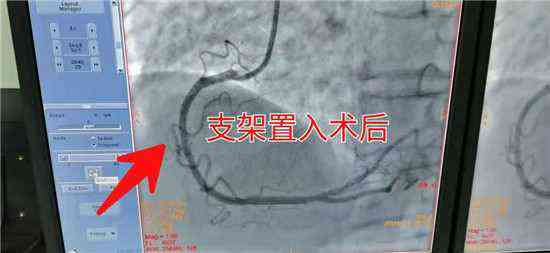

近日,新邵縣人民醫(yī)院急診科接來(lái)一位85歲,胸痛、胸悶的老人,根據(jù)其癥狀及臨床表現(xiàn),醫(yī)生初步診斷為急性心肌梗死。病情就是軍令,迅速為患者完成各項(xiàng)檢查,第一時(shí)間送入介入科搶救。五分鐘內(nèi)各路人員迅速到位,迅速給患者擺體位、上監(jiān)護(hù)、消毒、鋪巾、穿刺、送管、造影一氣呵成。冠脈造影顯示患者為急性下壁心肌梗死,需緊急為患者置入支架 打通血管。時(shí)間就是心?。£P(guān)鍵在此一搏,在家屬的積極配合下,迅速談話簽字,一切準(zhǔn)備就緒。

介入醫(yī)生輕舞導(dǎo)絲、細(xì)捻導(dǎo)管、聚精會(huì)神,半小時(shí)內(nèi)一枚冠脈支架有條不紊的送到了老人病變血管部位,為患者冠脈血管架起了一座圓形橋梁。堵塞的血管道路通了,心肌得到了有效的灌溉,血液歡快的流淌著,唱著生命的歌。